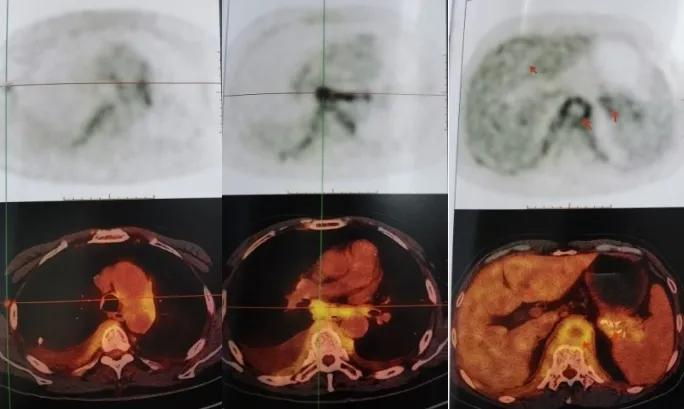

5、PET/CT检查

这是患者2020年9月15日在上海市某三甲医院行PET/CT检查影像学资料(图5a 5b):

图5a.上海市三甲医院胸部CT平扫(2021年5月28日)

图5b.上海市某三甲医院PET/CT检查(2020年9月15日)→:腹主动脉壁、胰腺体尾部、肝囊肿

炎性病变累及右侧颈部、锁骨区淋巴结(较大者10*8mm,SUVmax 5.35),纵隔、双肺门淋巴结(较大者位于纵隔7组,大小约23*20mm,SUVmax 5.85)、右侧腋窝淋巴结(较大者10*7mm,SUVmax 3.31)、腹盆腔淋巴结、腹膜后淋巴结及左肺上叶、双侧胸膜、膈肌、脾门处可能;双侧胸水;右肺上叶陈旧灶;肝脏囊肿,痔疮可能;垂体瘤可能(大小约10*9mm)。